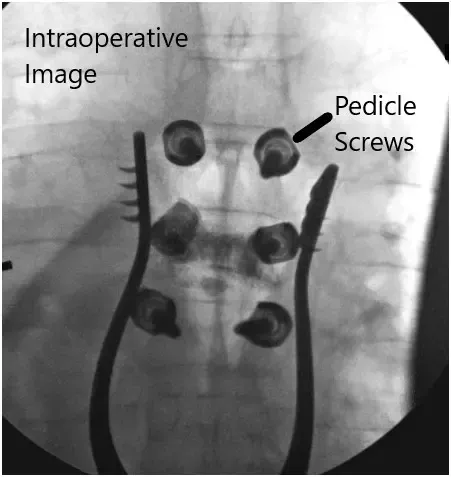

Imágenes fluoroscópicas intraoperatorias.

Siguiendo trayectorias anatómicas, luego tocamos estos pedículos para empezar e insertamos tornillos pediculares de 4,5 x 30 mm a ambos lados. Confirmamos nuestras trayectorias mediante fluoroscopia y activamos EMG. Hicimos lo mismo con los pedículos T5 y T7, sondeándolos con palancas de cambios Lenke y bajo fluoroscopia tras crear nuestro agujero piloto con puntos anatómicos normales de inicio con el taladro de alta velocidad. Insertamos tornillos de 5,5 x 40 mm bajo fluoroscopia directa en los niveles T5 y T7 y luego aplicamos varillas de 5,5 x 65 mm, que se aseguraron con tornillos de tapa y se bloquearon en su posición.

Los seis tornillos fueron estimulados con electromagnetismo electromagnético de disparo y se comprobó que estaban en una posición segura. Luego obtuvimos tanto la radiografía final de la AP como la radiografía lateral para asegurar la correcta posición de los tornillos. La herida se lavó abundantemente con irrigación con bacitracina y luego se utilizó el taladro de alta velocidad para decorticar el hueso, recogiéndose, mordiendo y usándose para autoinjertos.